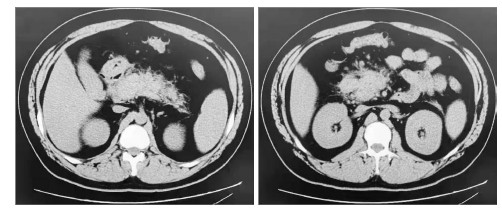

病情演变:患者病情进展快,入院时已有消化、循环、神经等多系统症状。诊疗重点:鉴别急腹症、心肺系统急症的不典型表现。入院后予以心电监护、胃肠减压、液体复苏,紧急完善相关实验室检查。血常规:白细胞14.14×109/L,中性细胞87.20%,中性粒细胞12.33×109/L。尿常规:隐血1+,蛋白2+,糖4+,酮体3+。血气分析:pH 7.15,PCO2 34 mmHg,PO2 75 mmHg,乳酸2.7 mmol/L,HCO3- 27.2 mmol/L;血糖18.7 mmol/L;Ca2+ 1.18 mmol/L,K+ 2.4 mmol/L。降钙素原1.1 ng/mL。肌钙蛋白I、肌酸激酶同工酶、N末端脑钠肽前体、肝肾功能检查均阴性。血尿淀粉酶轻度升高。凝血功能:纤维蛋白原739 mg/dL,D二聚体13 500 ng/mL,乳糜血。甘油三酯(triglyceride, TG)17.98 mmol/L。心电图:窦性心动过速,电轴左偏,心率130次/min。心脏、腹部超声:(1)心内结构大致正常,室壁运动正常;(2)胸腔少量积液;(3)胰腺体积大,回声不均,肝周积液。胸部、腹部CT(图 1):(1)两肺下叶炎症;(2)胸腔少量积液;(3)脂肪肝;(4)急性胰腺炎。

| 左图为胰尾渗出、肿胀;右图为胰头肿大,胰腺棉絮样渗出,肝区积液 图 1 患者入院时上腹部CT |

依据患者腹痛、急性胰腺炎影像、乳糜血、TG > 11.30mmol/L、排除占位和结石等其他病因并参考Balthazar CT分级,疾病诊断:HTG-AP(中度重型)、糖尿病酮症酸中毒、肺部感染、低钾血症。因存在有效循环血容量不足、胰性脑病等表现,病情重,遂收住EICU。